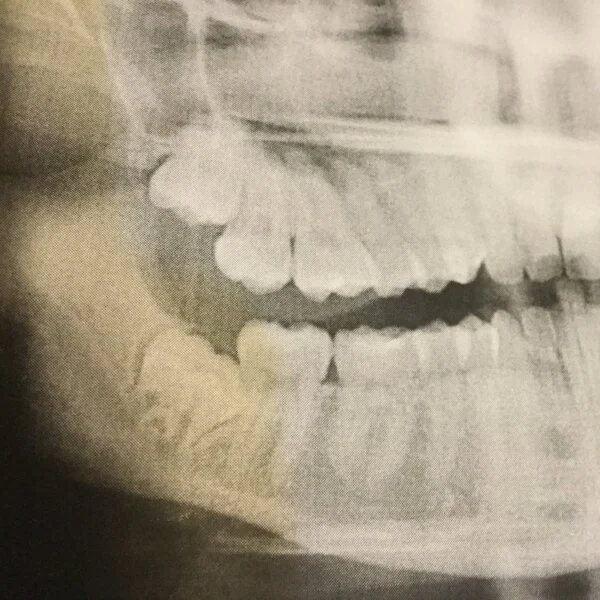

Wisdom teeth can become painfully impacted and create problems for other teeth.

Wisdom teeth

Wisdom teeth appear between the ages of seventeen and twenty-five. They can be quite painful, and most young people have them removed because they’re impacted, won’t fit in the mouth, or come in at an odd angle.

Before having them removed, if wisdom teeth try to break through the surface, it can be tremendously annoying. They can also cause cysts, decay or crowding of adjacent teeth. We talk more about removal here.